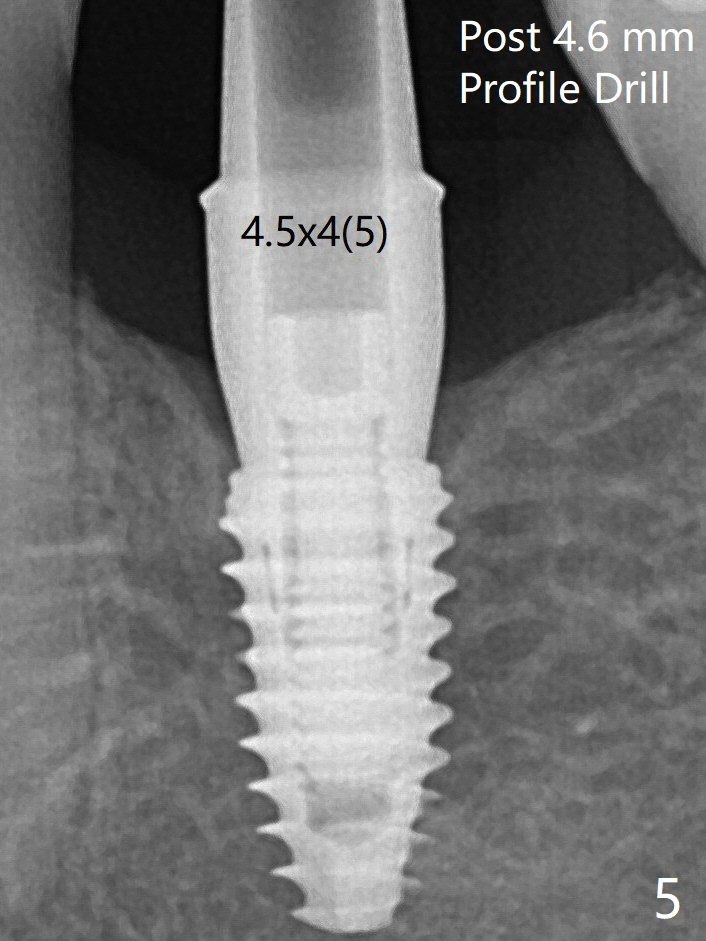

局麻下使用4.6毫米Profile钻头后(去除软硬组织阻挡),4.5毫米修复基台顺利就位(图五)。手拧紧螺丝顺手,不发出响声。因此第一次手术应该使用Profile钻头。